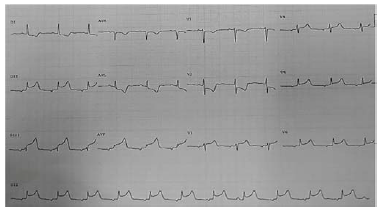

Um paciente de 55 anos de idade chega ao pronto-socorro com dor torácica há três horas, dispneia e sensação de sufocamento. Ao exame físico, apresentava-se em Killip III. Foi solicitado eletrocardiograma, demonstrado na imagem.

Um paciente de 55 anos de idade chega ao pronto-socorro com dor torácica há três horas, dispneia e sensação de sufocamento. Ao exame físico, apresentava-se em Killip III. Foi solicitado eletrocardiograma, demonstrado na imagem.